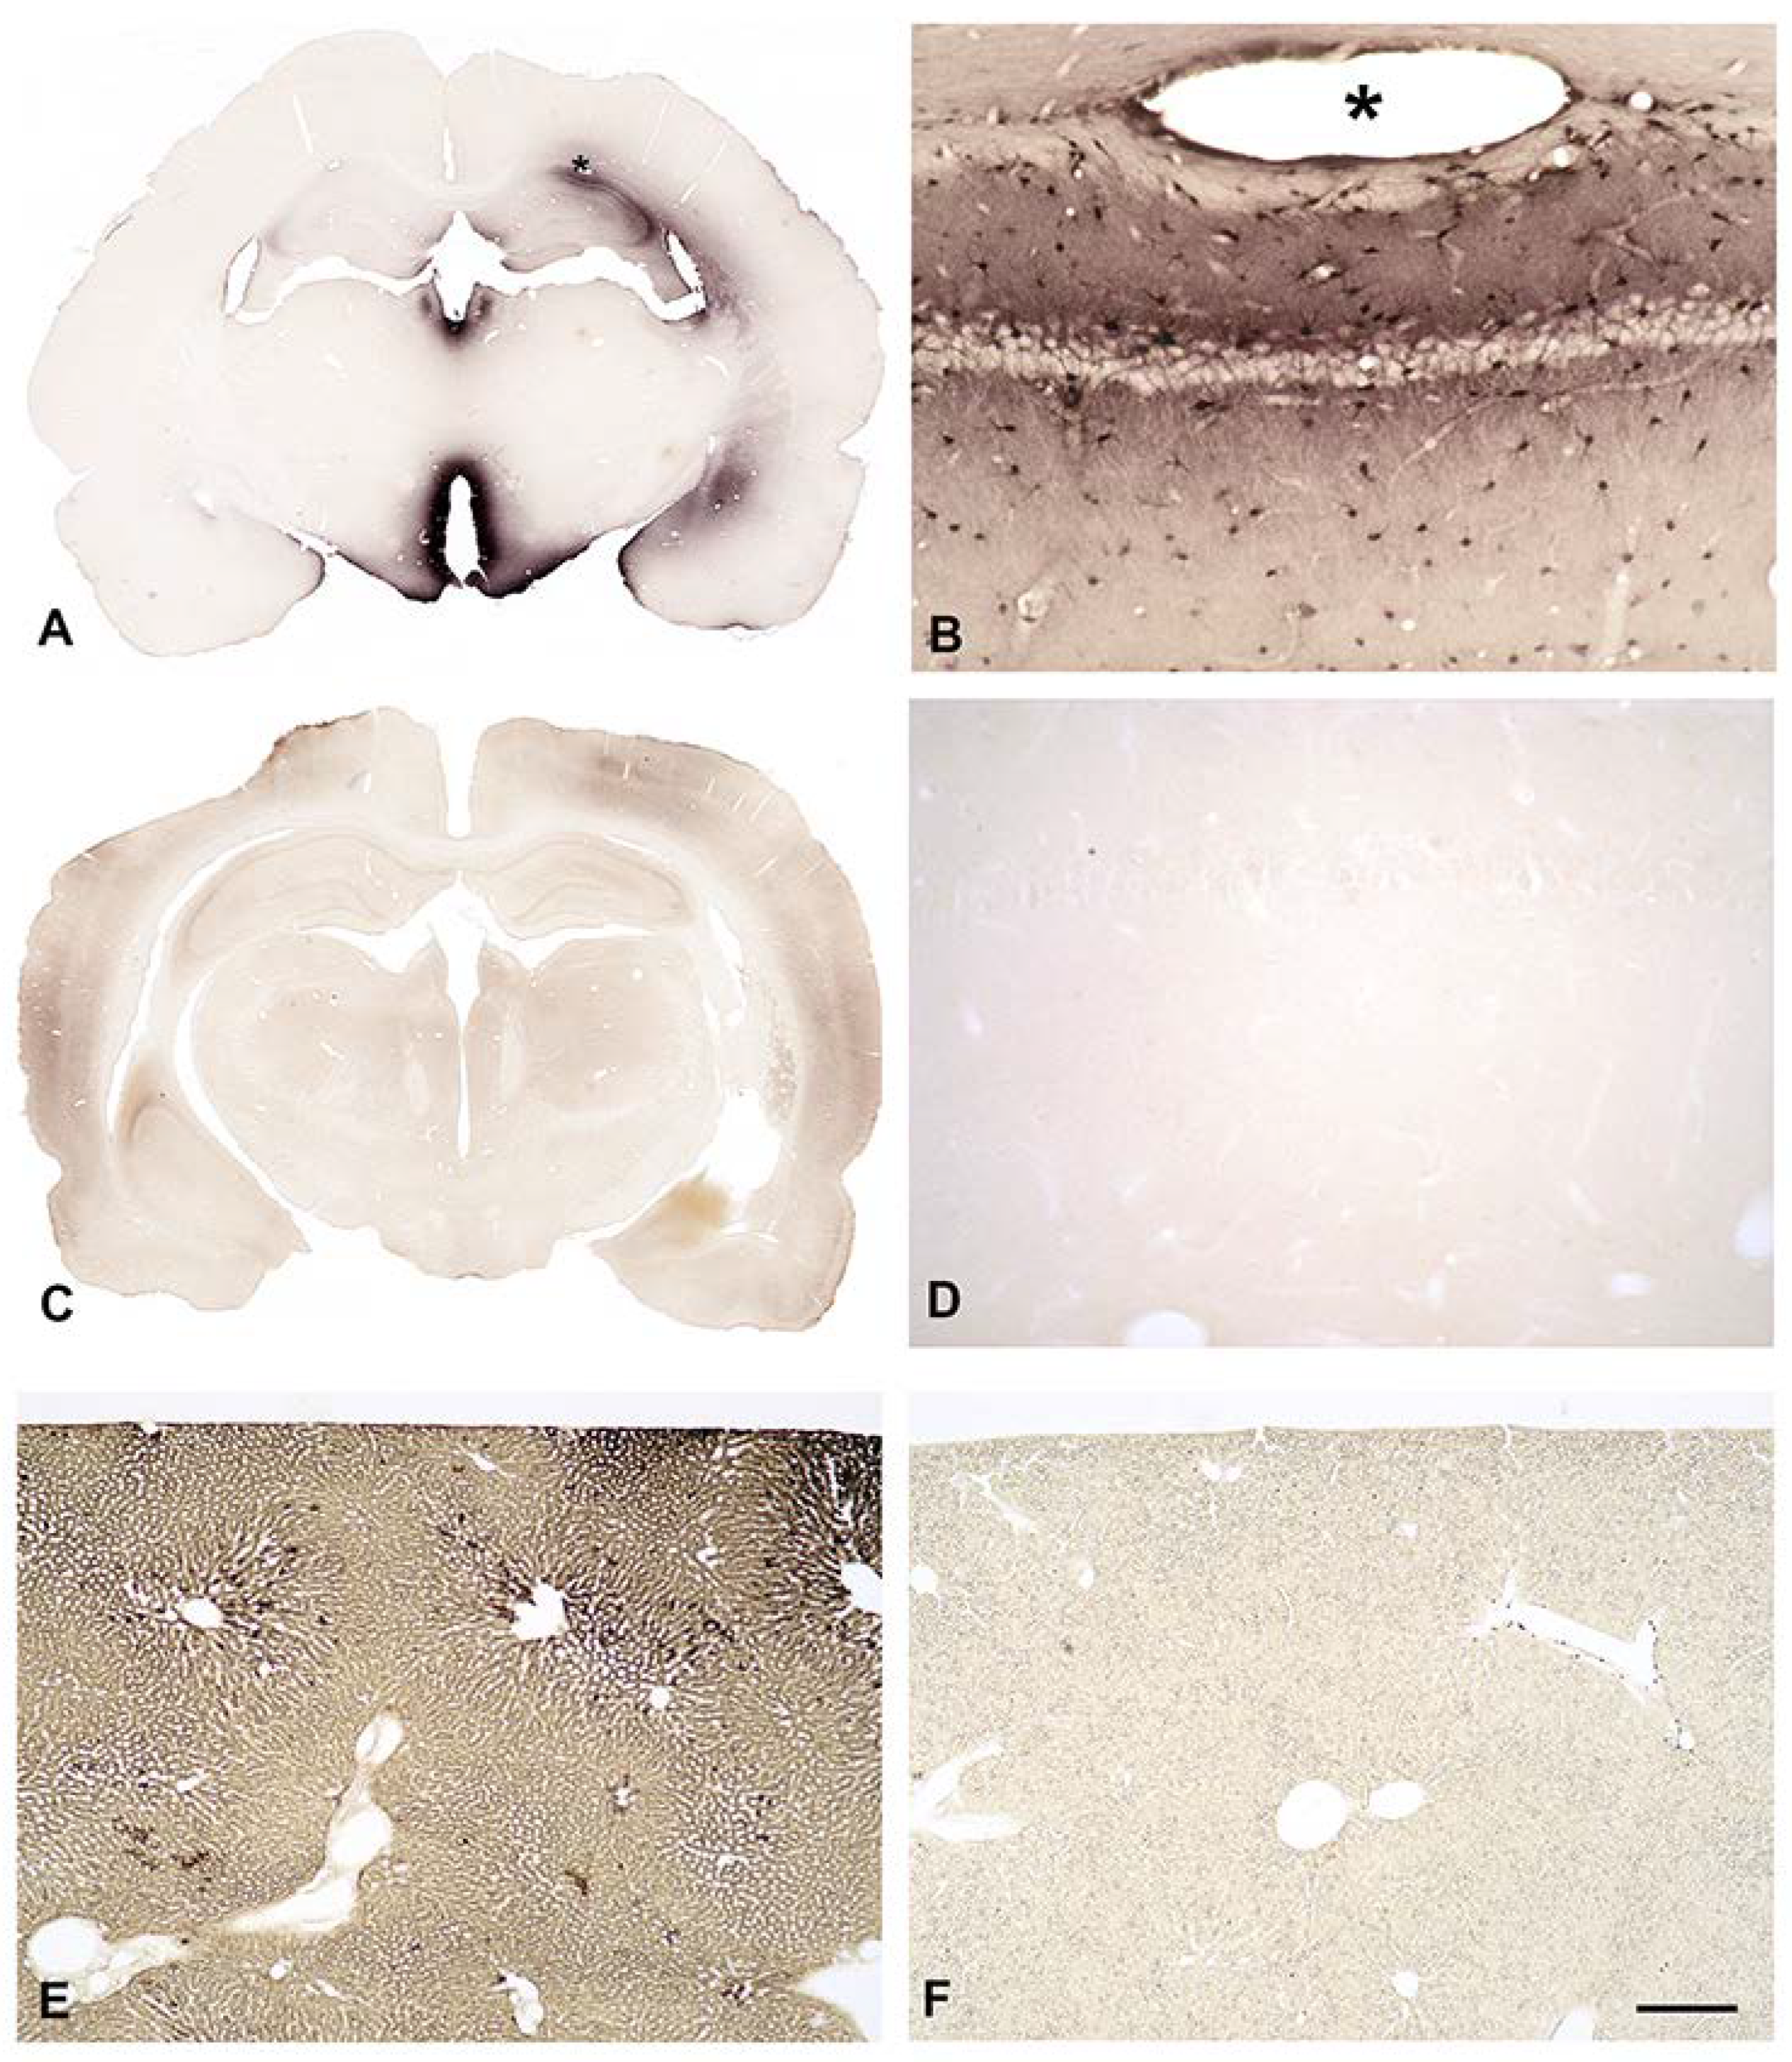

3.5. In Vivo Uptake of Native or Biotinylated SPM into the Brain from Intraventricular CSF or from the Bloodstream

3.7. In Vivo Uptake of Biotinylated SPM into the Brain from Intraventricular CSF

3.8. In Vivo Uptake of Biotinylated SPM into the Brain from the Bloodstream

4.4. Native or Biotinylated SPM Are Not Taken up into the Brain from the Bloodstream